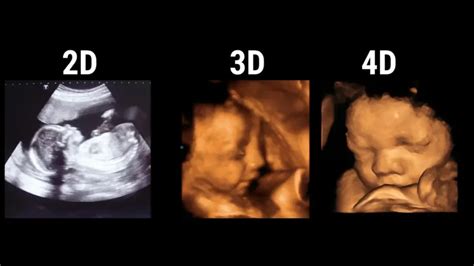

2d vs 3d vs 4d

2d vs 3d vs 4d. There are some references to 2d vs 3d vs 4d in this article. If you are looking for 2d vs 3d vs 4d you've came to the right place. We have posts about 2d vs 3d vs 4d. You can check it out below.